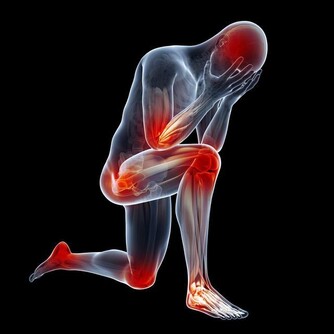

在你看來,打嗝除了讓自己感覺不大舒服之外,最大的後果也就是影響自身形象,可能讓自己看起來不太淑女,或者不夠紳士。其實這通常是件好事,讓你感到舒適,並表示你的消化系統正在發揮作用。

然而,如果你過度打嗝,這絕對值得關注。

如果你打嗝到令人煩惱的程度且每週出現三次及以上,就應該去看醫生了。

雖然打嗝幾乎不會是疾病的徵兆,但反复打嗝,尤其是與下列症狀一起發生時,可能意味著嚴重的健康問題。

如果打嗝出現得很突然,並伴有噁心和大量的嘔吐,這種情況的出現可能會危及生命。如果你不能減少打嗝的次數,並且還伴有胃脹和胃疼,可能意味著你患上了腸梗阻,在這種情況下,你需要馬上就醫。

2. 你感覺超級腹脹吞嚥下過多的空氣可能會導致胃部膨脹,但如果你的胃部非常脹並且疼痛,則可能是患上了梗阻。儘管如此,腹脹也並不一定就很嚴重,腹脹也可能是因為發生了腸易激綜合徵和乳糖不耐症,這兩種情況也會讓人出現打嗝。

3. 你的肋骨疼得厲害

食道裂孔疝是一種胃的一部分通過食管裂孔進入食道的疾病,可導致反复打嗝。就其本身而言,裂孔疝不是緊急情況,但它可能讓你非常不舒服。當疝氣切斷腹部其他部位的血液供應時,疝氣也會變得“絞亂”。這時候需要緊急手術,如果不及時治療後果可能是致命的。

4. 你的喉嚨著火了

如果你總是在飯後打嗝,打嗝的味道就像胃酸,且會感覺胸部有燒灼感,那麼你可能出現了胃食管反流的情況。頻繁的胃酸反流並不好,會對食道造成傷害。

5. 你莫名其妙地減重

體重迅速下降且伴隨著打嗝,是腸道阻塞的標誌。如果你本來不打算減肥,體重卻在快速下降,則可能意味著你的身體沒有正確地消化你所吃的食物,醫生可能會檢查你是否患有如腸易激綜合徵、食物過敏或克羅恩病在內的疾病。另外,打嗝與體重下降同時出現,也很可能是胃癌的徵兆。